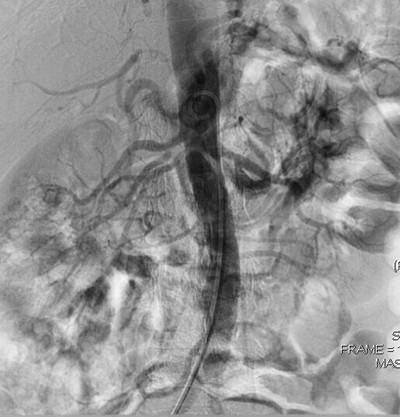

近日,我院放射科成功完成一例复杂型肾动脉狭窄介入治疗。患者,女,39岁,以“高血压”就诊,血压最高时达172/115mmHg,CT检查发现双肾动脉狭窄,且右肾为两支肾动脉(主肾动脉、副肾动脉各一支)均狭窄,副肾动脉重度狭窄(狭窄率达90%)。经过术前积极准备,放射科主任张来安主治医师、李继兵主治医师为患者实施了肾动脉球囊扩张介入治疗,为了达到最好疗效,术中对三支狭窄肾动脉均进行了球囊扩张。术后一周,血压即恢复到了正常。经过近期随访,患者血压稳定在125/85mmHg。

肾动脉狭窄是引起高血压的常见原因,老年患者多为粥样斑块导致狭窄,青中年患者以动脉炎或肌纤维结构不良导致狭窄为常见。传统治疗方式一是药物降压,但血压往往不易控制在正常范围,且无法解除肾动脉狭窄;二是外科手术肾动脉旁路移植,但创伤大,费用高,并发症多。随着近年介入治疗的兴起和成熟,肾动脉狭窄首选介入治疗。该方法只需穿刺股动脉,引入导丝、导管、球囊或支架等介入器材至肾动脉,用球囊扩张狭窄处(或植入支架)即可,术后效果立竿见影。